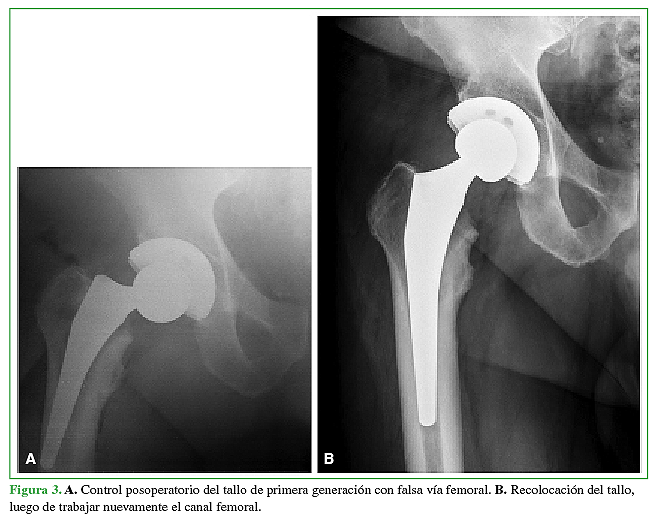

Al evaluar al grupo 1, contemplando el primer año de seguimiento posoperatorio, se produjeron dos (2,44%) complicaciones durante la cirugía. La primera fue una fractura de calcar, que se resolvió colocando una lazada de alambre en el mismo momento, evaluando la estabilidad inicial con la raspa de prueba y luego colocando el tallo definitivo (Figura 2). La segunda complicación fue una falsa vía generada mientras se trabajaba el canal femoral (Figura 3A), la cual se resolvió a las 24 h, en un segundo tiempo quirúrgico, con el correcto reposicionamiento del mismo componente primario (Figura 3B).

A. Control posoperatorio del tallo de primera generación con falsa vía femoral. B. Recolocación del tallo,luego de trabajar nuevamente el canal femoral.